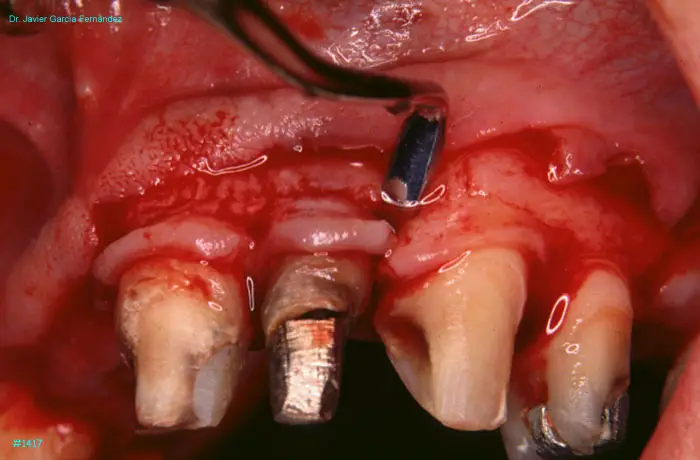

Atlas of Surgical Techniques in Periodontics. Chapter III. Atlas de Técnicas Quirúrgicas en Periodoncia